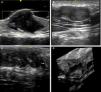

Skin ultrasound with high resolution probes (20-22MHz) enables diagnostic confirmation of superficial neurofibromas quickly and noninvasively. The presence of well-defined hypoechoic masses in the dermis (cutaneous neurofibromas in the dermis), irregular dermohypodermal regions (diffuse subcutaneous neurofibromas), or regions with oval or beaded morphology (subcutaneous nodular neurofibromas) is characteristic in subcutaneous cell tissue, with the intralesional Doppler images of showing tenuous or absent vascularization (Fig. 11).50,51

High-resolution ultrasound image (20MHz) of different neurofibromas. A. Cutaneous superficial neurofibroma where a well-delimited hypoechoic area can be seen in the dermis with a minimal Doppler signal (red color). B. Nodular subcutaneous neurofibroma of the patient in Fig. 9, in which a bilobulated, well-delimited, heteroechogenic lesion can be seen with mild posterior reinforcement that follows the path of a laterocervical peripheral nerve. C. Subcutaneous neurofibroma that occupies the subcutaneous cell tissue and deep dermis in which diffuse areas (*) and chordal areas (**) can be observed. D. Three-dimensional ultrasound reconstruction in which a convoluted linear area can be seen associated with thickening of a peripheral nerve.